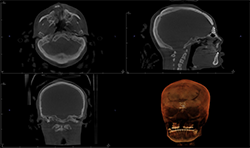

Case 3: 18-year-old woman with cleft for orthognathic surgery

Panoramic and cephalometric radiographs are of limited use due to superimposition of anatomical structures (Figs. 5A, 5B, 5C).

CBCT characterizes the cleft defect more superiorly than 2D imaging (Fig. 6).

The Planmeca Viso G7 CBCT unit and Planmeca Romexis software can stitch two volume scans automatically with one click. The top portion of the skull (Fig. 7A) and the remaining maxillofacial portion (Fig. 6) were stitched to make a single skull volume (Fig. 7B). Multidisciplinary team has been working on this patient. Prosthodontics and oral surgery will plan to manage maxillary alveolar cleft and associated malocclusion following the CBCT images.

Fig. 7A

Fig. 7B